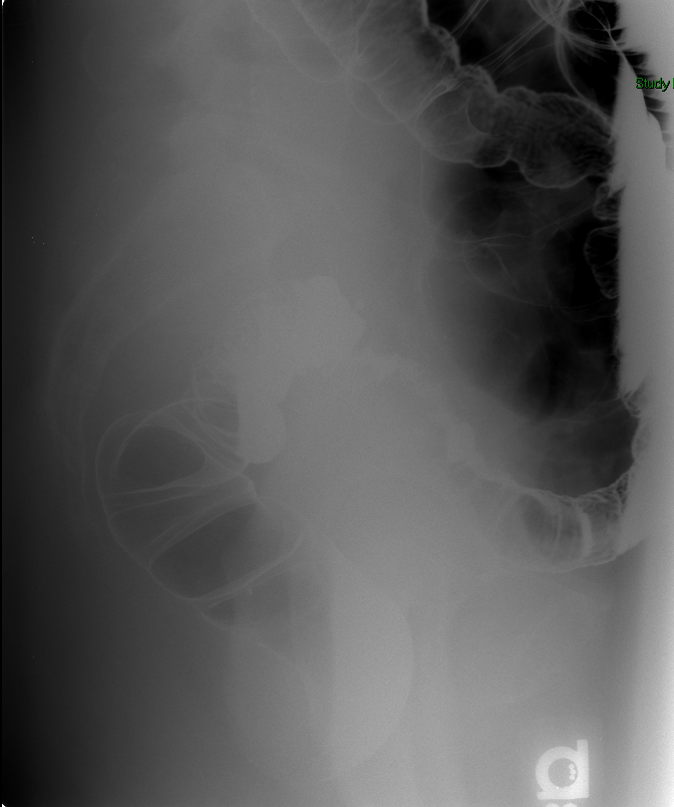

- The technologist will obtain a scout image. Assess the image for any possible contraindications such as pneumoperitoneum, evidence of ileus or obstruction, or residual contrast material

(key image 1).